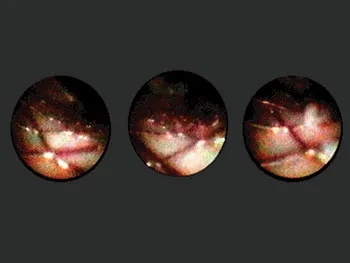

July 1999 was for me the discovery of stents with a permanent coating eluting called Rapamycin at the headquarters of Cordis Johnson and Johnson. Our first experience was in Rotterdam and in Sao Paulo with the Cypher® Stent. And of course, the Cypher stent for a few years overshadowed any development in the field of biodegradable scaffolds. It is Hans Bonier, one of my ex-trainees, who drew my attention to the idea of a German Professor of Cardiology, Heublein, who had developed the concept of a metallic bioresorbable stent using magnesium. I found the idea fascinating, but obviously, Biotronic being a German company, the technology went to Raymund Erbel and Michael Haude in order to be investigated. I followed the development and gave my advice to them on several occasions. So when Abbott made known that they were ready with their first bioresorbable scaffold, the so-called ABSORB Cohort A, the first iteration of an everolimus bioresorbable scaffold, I was fully committed to investigate that product the best I could. John Ormiston had the privilege to perform the first historical implantation. At the Thoraxcenter, we implanted 16 of the first 30 scaffolds. And from the very beginning, I used the combination of optical coherence tomography, virtual histology, grayscale intravascular ultrasound, angiography, and multislice CT scan to assess the results (Figure 1.1.1). Later on, it appeared that this combination of invasive and noninvasive imaging was essential and critical in the understanding of the bioresorbable concept. Yoshi Onuma joined me at that time and became instrumental in collecting and analyzing the 6-month and 2-year results of the Cohort A. We came to the conclusion that the integrity of the device was subsiding too quickly and could not counteract fully the constrictive reaction of the vessel wall following the barotrauma of the implantation. A second iteration was designed since the late loss with the first device was 0.44 mm, a loss judged by myself unacceptable, taking into account that even a stent like the Taxus® stent had a loss of 0.39 mm [3,4]. The second generation, the so-called ABSORB Cohort B, was a real success in the sense that we lowered the late loss to 0.23 mm with long-term results that were mimicking the results of Cohort A [5]. From Cohort A, although the results at 6 months were not acceptable, we learned that the later follow-up with positive remodeling and late lumen enlargement had tremendous potential and should be duplicated by this second iteration device, providing a better late loss could be obtained. This was going to be achieved with Cohort B1 and B2.

Figure 1.1.1Angioscopy of a coronary artery with a wall stent implanted showing prolapse of tissue trough the struts.